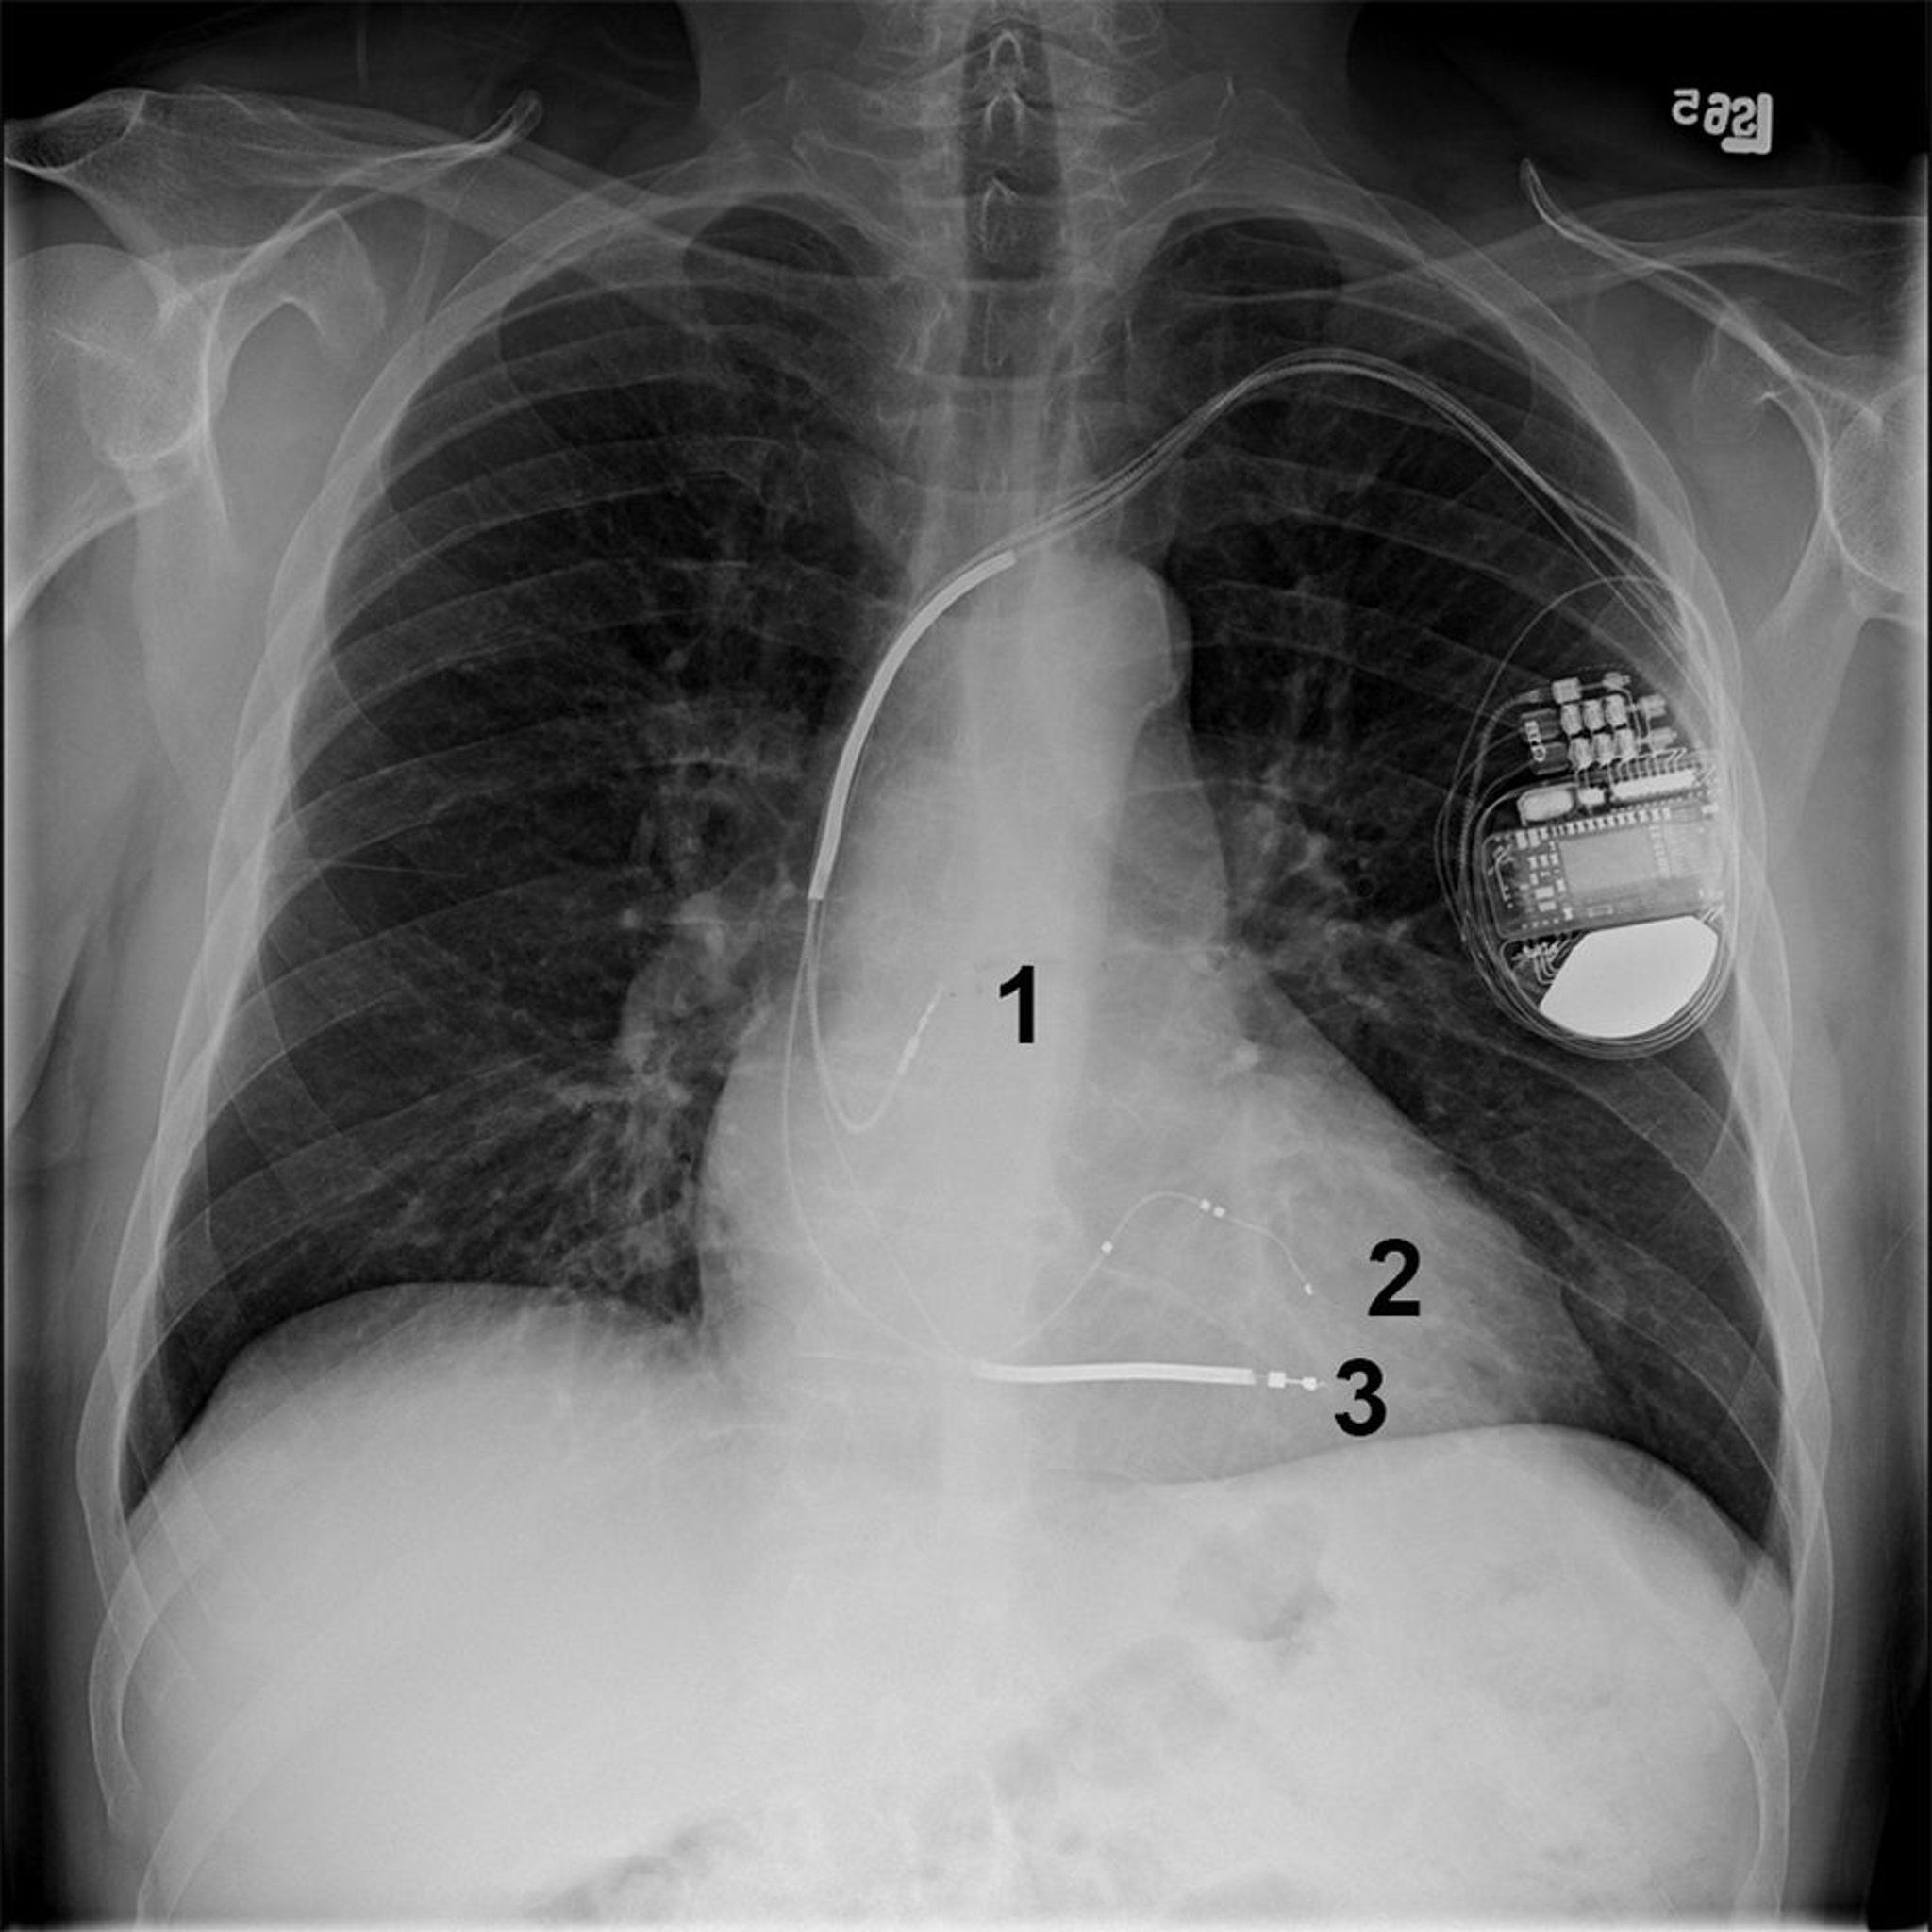

Radiografía torácica de un paciente con un desfibrilador cardioversor implantable (DCI) biventricular (bi-V)

Este paciente tiene un cardiodesfibrilador implantable biV en la parte superior izquierda del tórax con derivaciones en la aurícula derecha (1), el ventrículo izquierdo (2) y el ventrículo derecho (3).